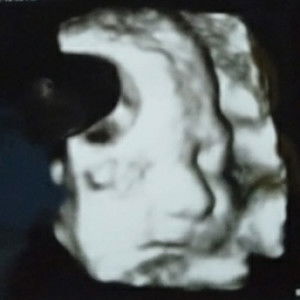

Kehamilan

Bun saya hamil 6bulan. Sekarang lbih sering buang air kecil. Kuranglbh 2jam psti kr kmr mndi lg. Bunda jg sprti itu tdk ya.. Normal tdk ta bun